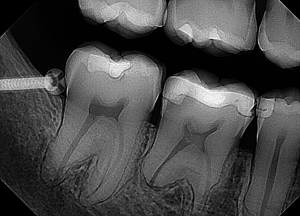

An example of a good X-ray image

When it comes to how your digital X-rays look, there is no right or wrong answer. As long as your images are diagnostic, then it really is “in the eye of the beholder.” Some doctors enjoy using the tools in the software to manipulate the images. This allows them to see things that they may have otherwise missed or ensures that they are really seeing what they thought they were seeing.

If your sensor can produce a great, good-looking image right off the bat and then you can make a few modifications to that image to get your perfect image, then you have a good, quality sensor.